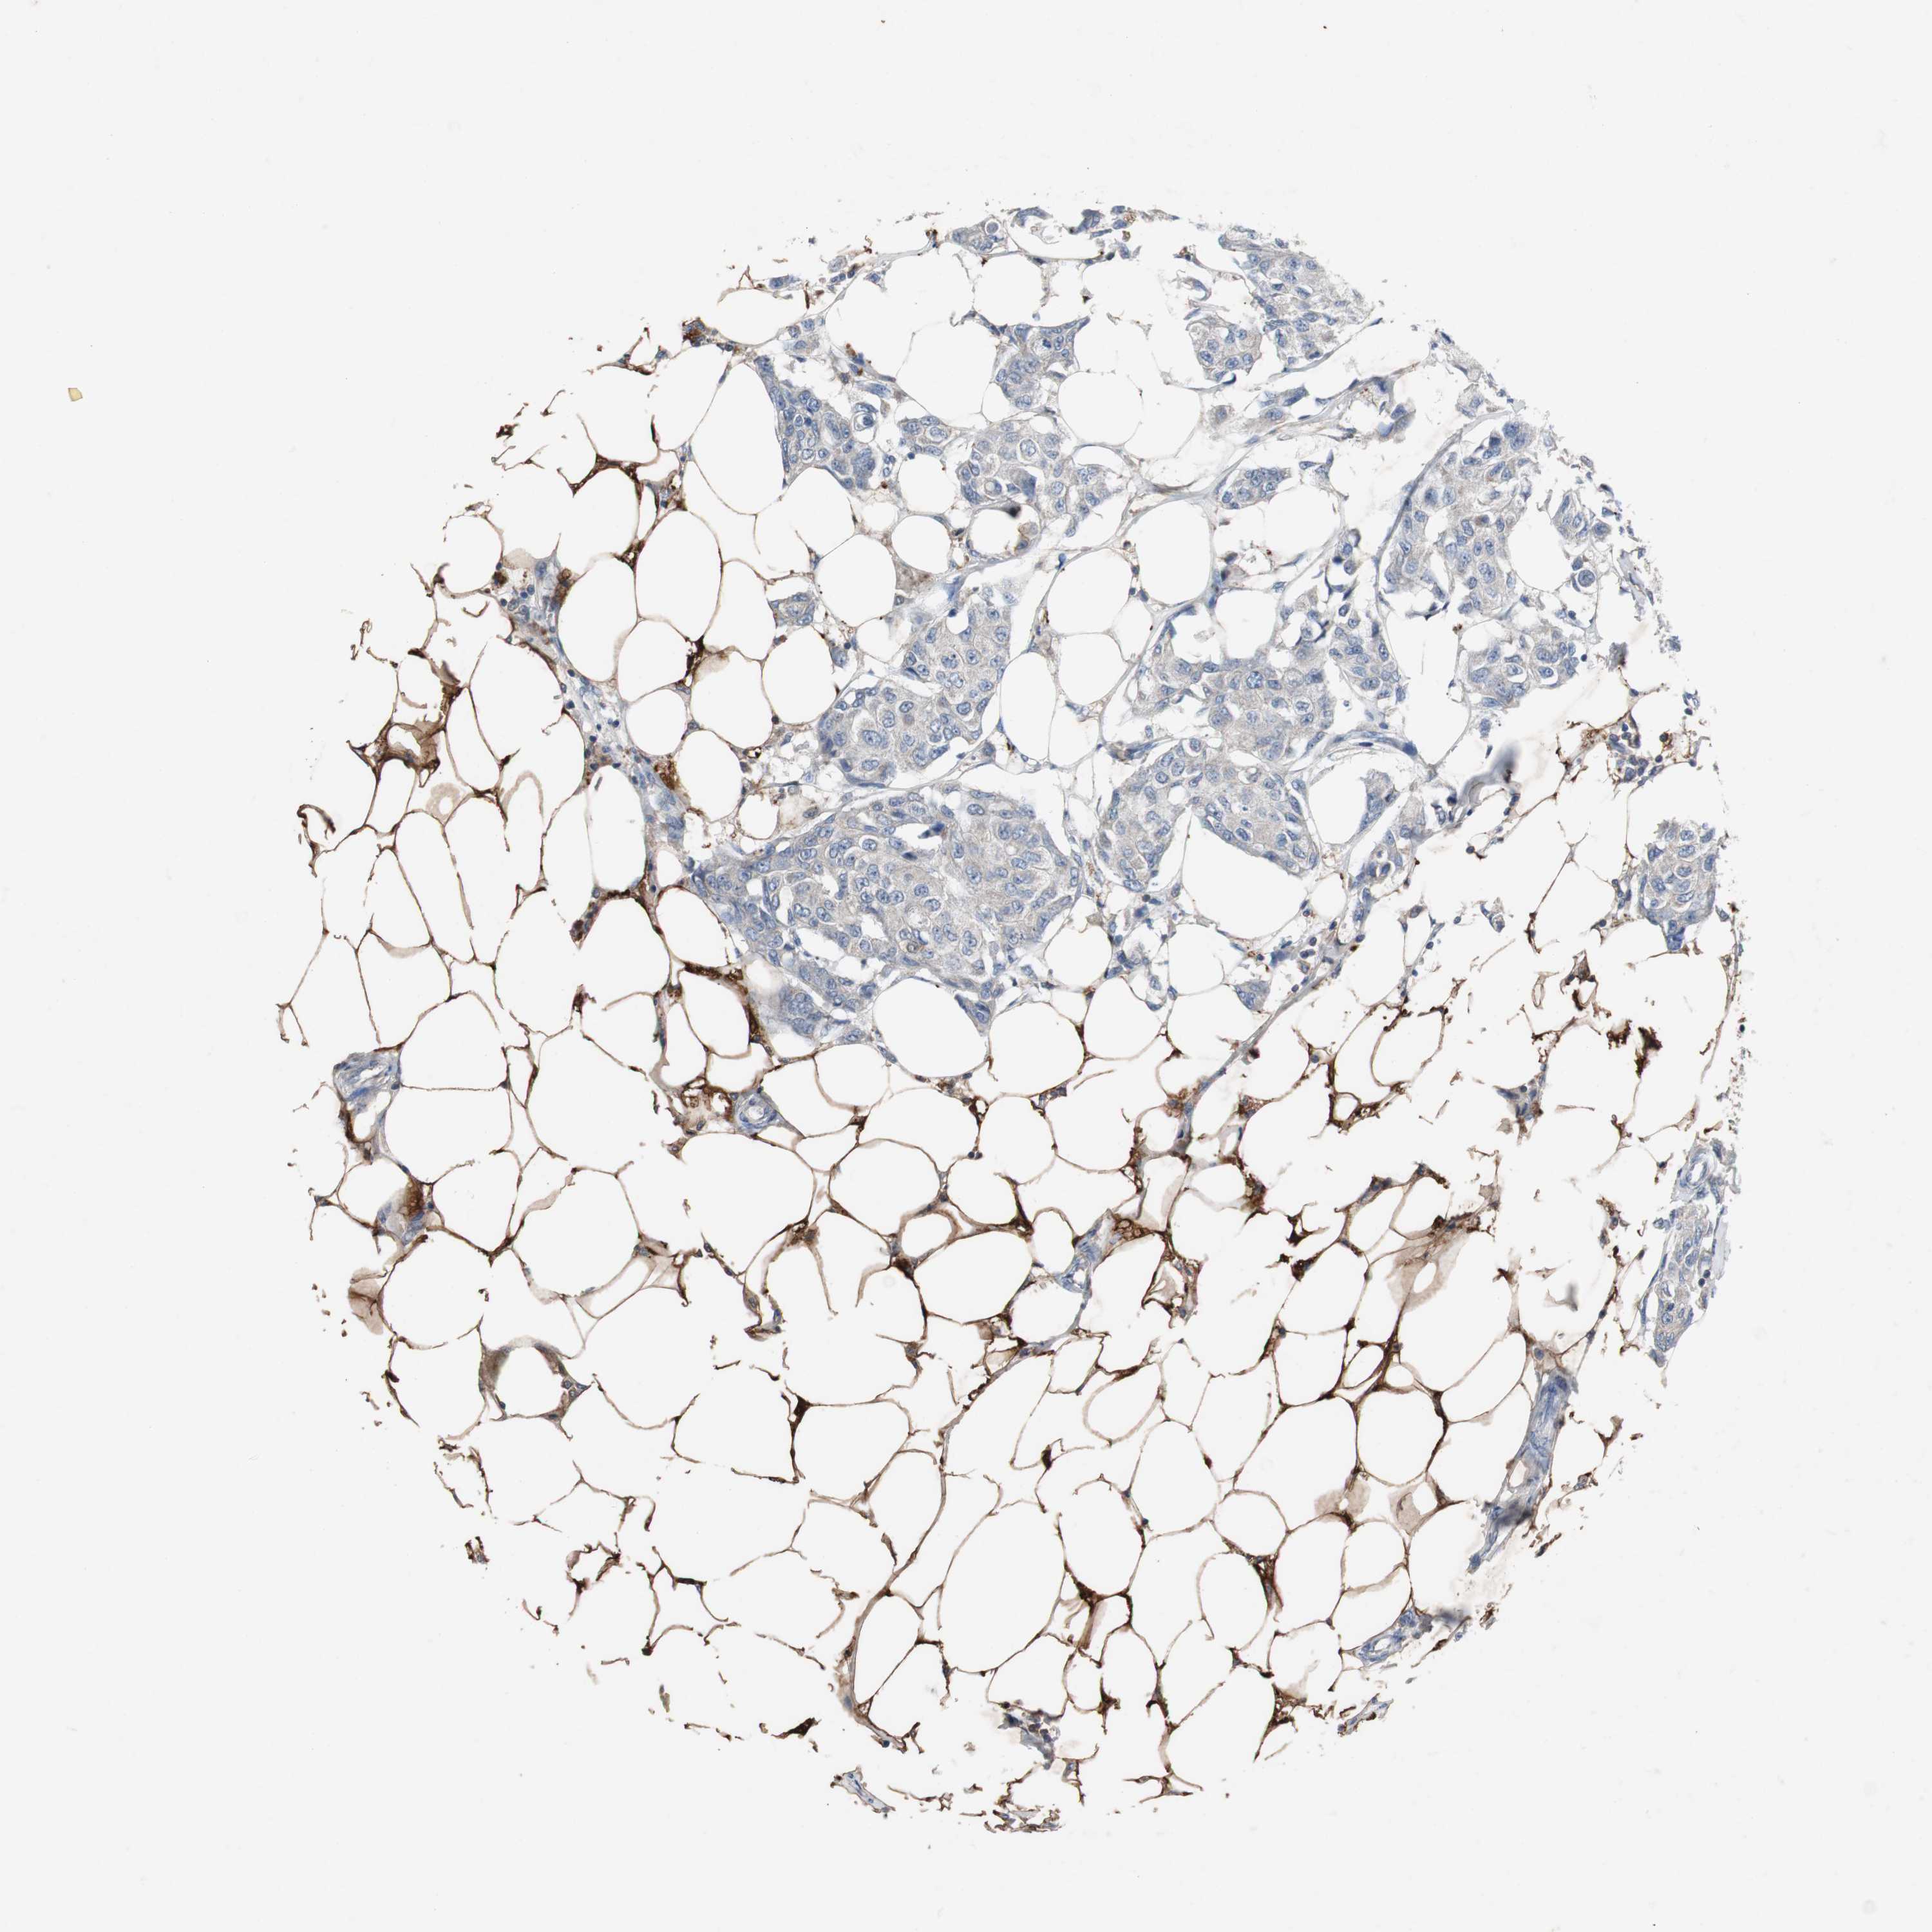

BRCA TCGA BRCA VALIDATION PROTEIN EXPRESSION

Breast cancer

Human cancer